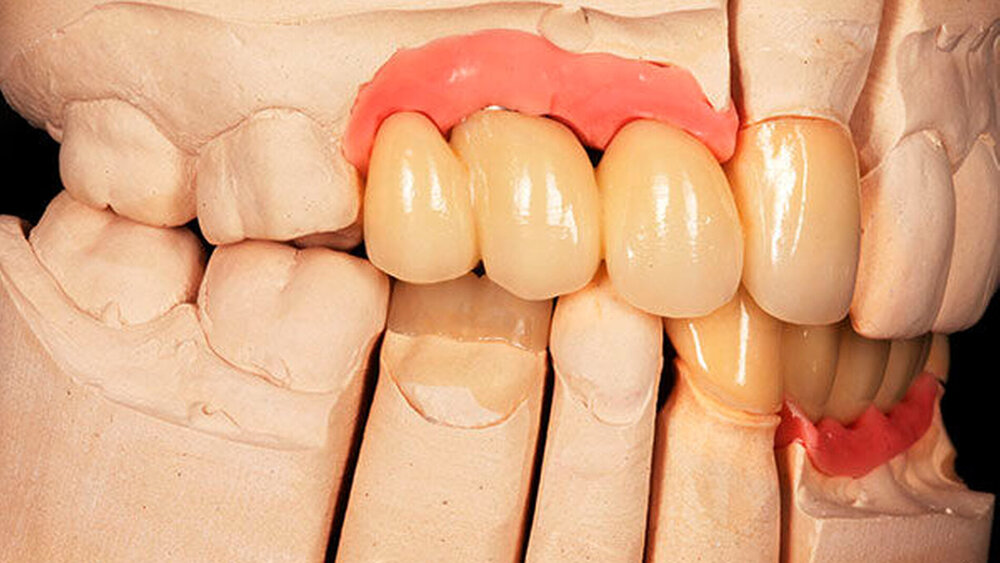

Die chirurgische Platzierung von Zahnimplantaten, das heißt die eigentliche Implantation, und die nachfolgende prothetische Versorgung dieser Implantate liegen nicht immer in einer Hand, sondern werden zum Teil von zwei verschiedenen Behandlern durchgeführt. Eine solche Arbeitsteilung hat durchaus Vorzüge: Aus der Allgemeinchirurgie wissen wir, dass Operateure mit großer Behandlungsroutine (hohe Fallzahlen pro Jahr) signifikant bessere Ergebnisse erzielen [Halm et al., 2002]. Doch geteilte Zuständigkeiten bergen auch Fallstricke: Wenn die Implantation und die nachfolgende prothetische Versorgung nicht gemeinsam geplant oder zumindest aufeinander abgestimmt werden, stellen sich im Fall eines ungünstigen Endresultats (Behandlungsfehler-Vorwurf) Fragen der Verantwortlichkeit. Man denke etwa an einen Fall, in dem ein Fachchirurg Implantate setzt, die aus Sicht des Implantatprothetikers falsch positioniert sind (Abbildungen 1, 2, 4, 5 und 6).

Letzterem bleibt nur die Wahl zwischen der Ablehnung der Weiterbehandlung und der Empfehlung einer aufwendigen und substanzverlustträchtigen Revision der Implantate (beides mutet dem betroffenen Patienten einiges zu) oder einer „Kompromissbehandlung“ mit dem Ziel, die invasive Revision der gesetzten Implantate abzuwenden und so den Schaden für den Patienten zu begrenzen. Heikel wird es insbesondere dann, wenn der Prothetiker in bester Absicht eine solche Kompromissbehandlung wagt, diese sich aber als nicht alltagstauglich erweist und der Patient schlussendlich Klage erhebt.

Hier kann es unter Umständen schwerfallen, die Verantwortung zuzuweisen: Liegt die Schuld beim Chirurgen, der die Implantate an ungünstiger Stelle gesetzt hat, oder beim Prothetiker, der sich nolens volens auf diese Situation eingelassen und ein letztlich unzureichendes Behandlungsergebnis erzielt hat? Aus fachlicher und ethischer Sicht ist die eigentliche Ursache für das insuffiziente Behandlungsergebnis beim Chirurgen zu suchen. Juristisch gesehen trägt dagegen jedoch der Implantatprothetiker die unmittelbare Verantwortung für das Behandlungsergebnis, da er die insuffiziente Suprakonstruktion geplant und eingegliedert hat. Rechtlich verhängnisvoll wird dieses Vorgehen insbesondere dann, wenn er den Patienten nicht explizit über den Kompromiss- und Versuchscharakter seiner Versorgung aufgeklärt hat oder das Aufklärungsgespräch und das Einverständnis des Patienten zur eigenen juristischen Absicherung nicht sorgsam dokumentiert hat.